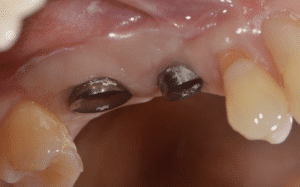

Fig.8 : Contrôle postopératoire à 10 jours.

Fig.9 : Mise en place de la couronne définitive.